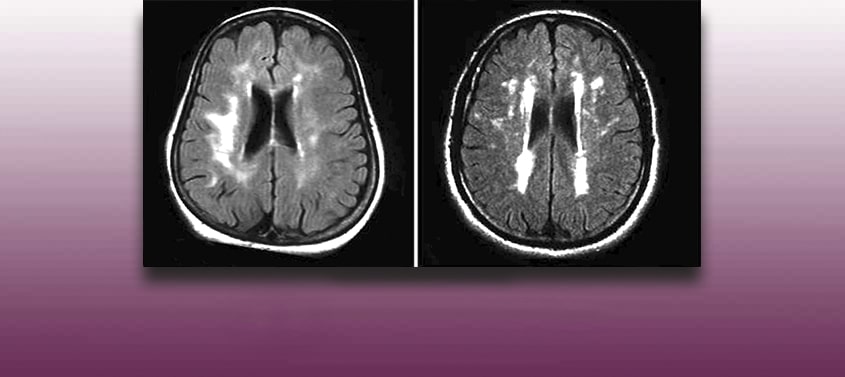

Zerebrovaskuläre Erkrankungen

Letzte Überarbeitung: 20/03/2026, Dr. med. Miguel B. Royo Salvador, Arztnummer: 10389. Neurochirurg und Neurologe. Definition Der Begriff „zerebrovaskuläre Erkrankung“ bezeichnet im Allgemeinen eine heterogene Gruppe pathologischer Zustände, denen eine fokale Funktionsstörung des Hirngewebes gemein ist, die auf ein Ungleichgewicht zwischen der Versorgung und dem Bedarf an Sauerstoff und anderen Substraten zurückzuführen ist. Er definiert den […]